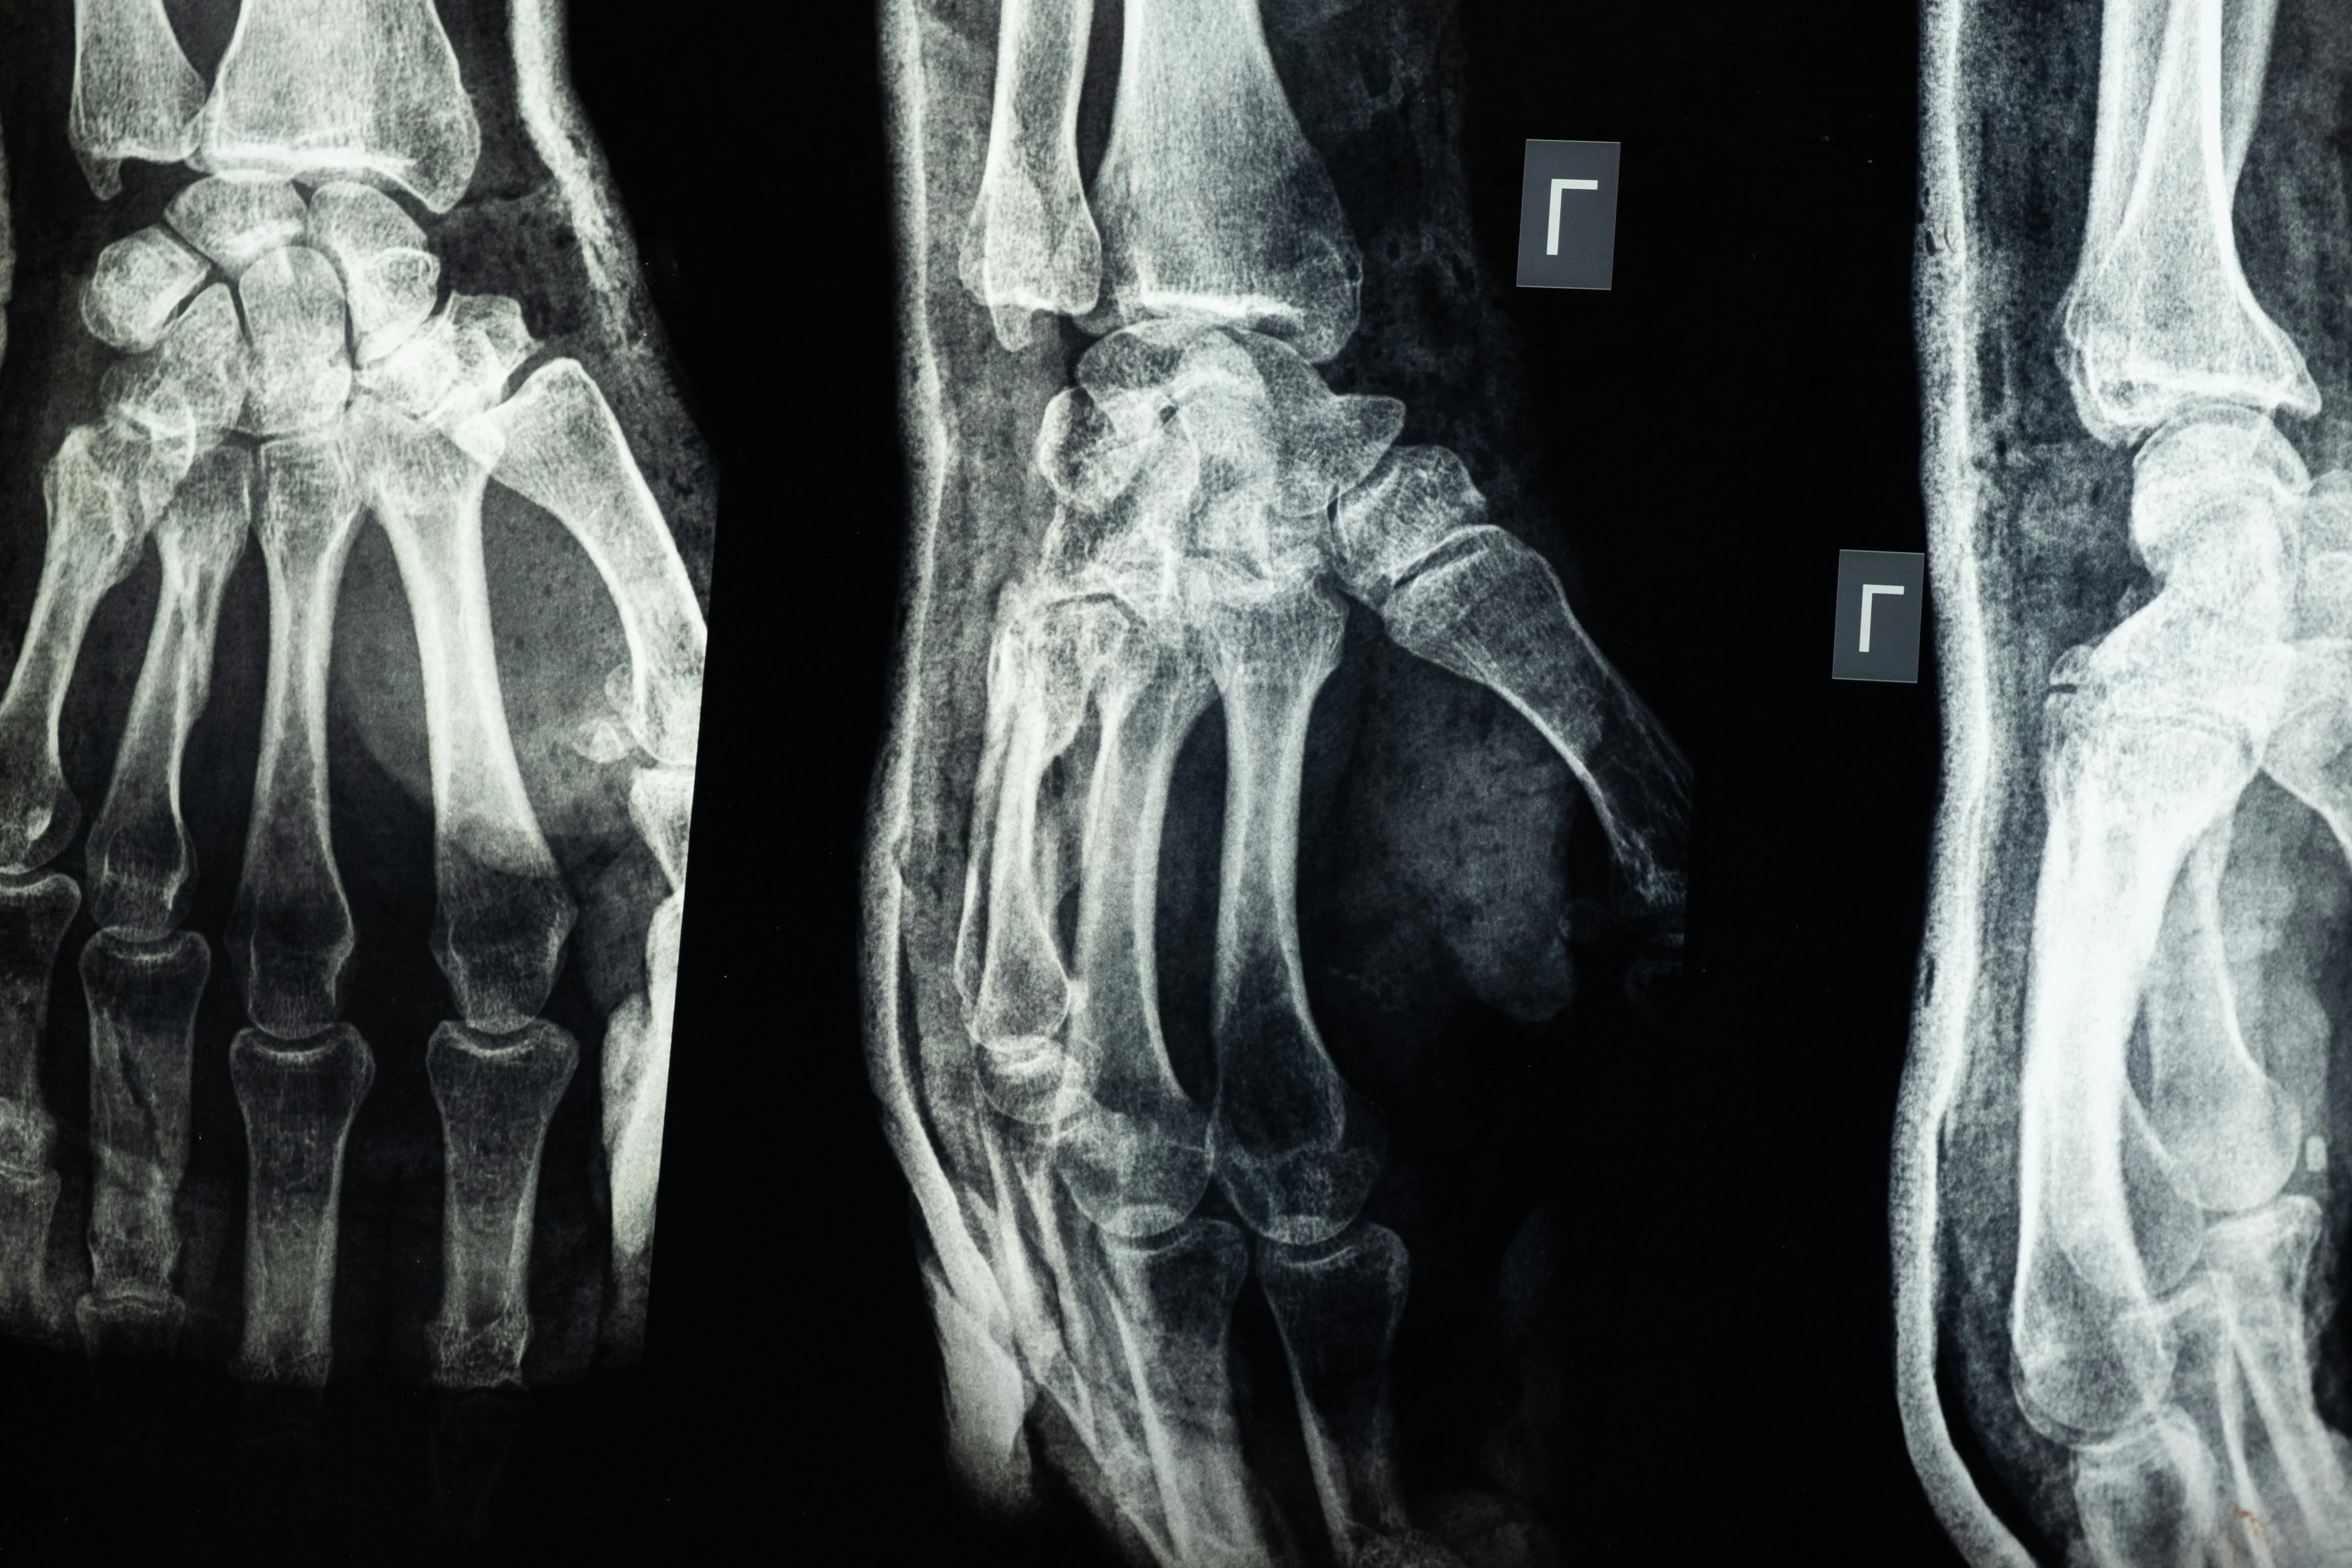

콘드로이친이란 무엇일까?

콘드로이친(Chondroitin)은 우리 몸의 연골과 결합조직 속에 자연적으로 존재하는 성분으로

관절 사이에서 충격을 흡수하고 마찰을 줄여주는 역할을 합니다.

나이가 들면서 콘드로이친이 점점 감소하면 관절이 뻣뻣해지고 통증이 생길 수 있다고 합니다.

그래서 외부에서 콘드로이친 보충제를 섭취하면 연골의 탄력을 유지하는 데 도움이 된다고 알려져 있습니다.